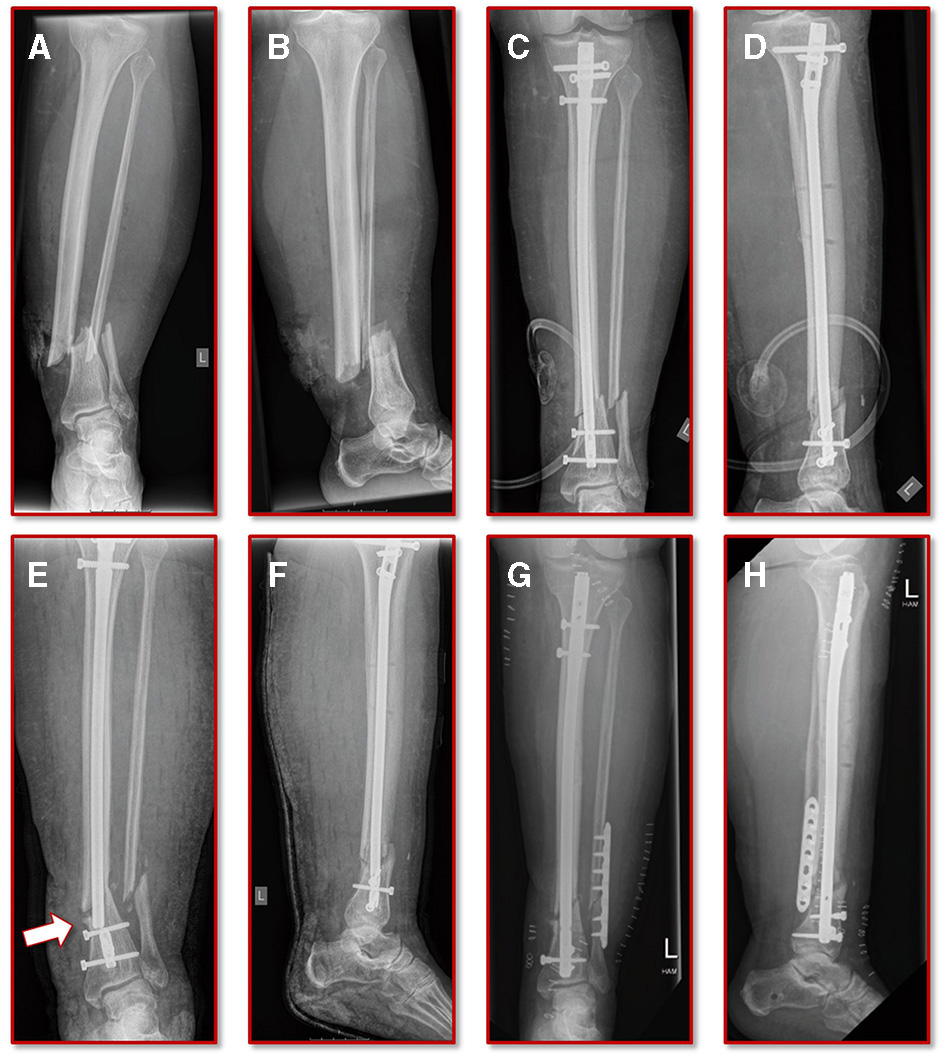

A 55-year old, female patient (height 152 cm, weight 73 kg) was treated for an open distal tibial shaft fracture (Figures 1A,B) with debridement, temporary external fixation, negative pressure wound therapy, unreamed intramedullary tibial nailing (8 mm diameter) (Figures 1C,D) and MESH graft skin closure at an external institution within the span of 4 weeks. Immediate post-operative full weight-bearing was ordered. Approximately 7 weeks after the tibial nail procedure was performed and without further trauma the patient suffered from an implant failure and refracture of the initial situation (Figures 1E,F). She was then referred for treatment to our institution, where after an initial hardware removal, temporary external fixation and histological and microbiological exclusion of infection, a reamed nailing procedure (9 mm nail diameter) and fibular plate osteosynthesis was performed (Figures 1G,H). Again, immediate post-operative full weight-bearing was performed and reached within the inpatient stay, as controlled with plantar pressure measurements (16). To estimate the non-union risk of the patient the Non-Union Risk Development (NURD) Score was calculated as 7 (17). Furthermore, the patient suffered from a severe Neurofibromatosis, that if counted as a chronic condition would increase the NURD score further to 9. The patient consented to the study. Only routine imaging data was used and the study was approved by the local ethics committee.

Figure 1

Initial clinical imaging. (A,B) a.p. and lateral view of the initial 2° open distal tibia fracture. (C,D) a.p. and lateral view after intramedullary tibial nail implantation and split thickness skin grafting, following temporary external fixation debridement and negative pressure wound therapy. (E,F) a.p. and lateral view after refracture and implant failure. (G,H) a.p. and lateral view after two-step exchange nailing and fibular plate osteosynthesis.